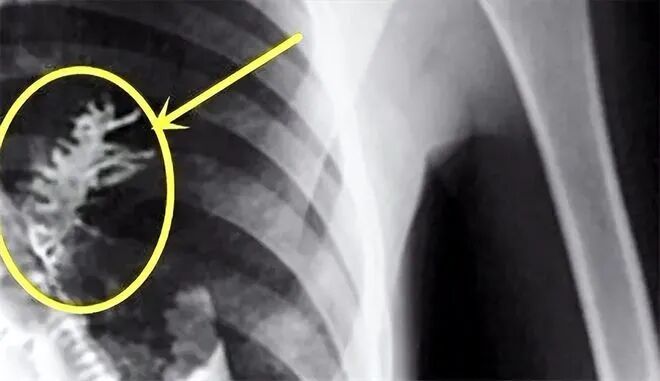

经过一系列专业精密的检查之后,医生表情严肃地指着X光片中肺部的一团阴影对亚特尤姆说:

“我们可以很确定地告诉您,您的肺部发生了病变,而且我们还发现了肿瘤,现在已经是肺癌的中晚期了。”

原来,在亚特尤姆的胸腔肺部里,并没有发现X光片中检查出来的癌症组织,反而是长着一颗小小的,生命力却很蓬勃旺盛的树苗。

眼前的景象令当场许多富有经验的医生护士感到错愕不已,因为这棵生在亚特尤姆肺部的树苗颜色翠绿,显然没有半分“营养不良”的样子,他认真去看那树苗,甚至能看见许多细细密密的针状树叶,看起来,品种或许是云杉或者冷杉。

卡马谢维医生当即惊讶的愣住了,甚至错以为是自己眼花,还特意向自己的医疗助手询问:“这是我的幻觉吗?我眨了好几次眼睛,确认无疑那是一棵小树苗?”

亚特尤姆胸腔中长了一棵树/资料图

现在,大家都知道造成造成亚特尤姆胸疼、咳血的罪魁祸首并非是癌症,而是一颗俄罗斯当地特有的冷杉或云杉树的小树苗,而且,这棵小小的树苗,已经生长到5厘米左右,几乎相当于成年人的一根手指。

就在树苗日渐长大的过程中,因为慢慢撑开的针状树叶戳到了亚特尤姆肺部的毛细血管,所以才会时不时地咳血和感到胸部异常疼痛。